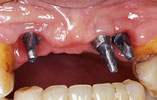

CASE2

上の前歯4本が欠損 審美的回復

インプラント埋入前

インプラント埋入後

インプラントに

セラミッククラウンを装着

上の前歯4本が欠損しており、以前は義歯が入っていました。3本のインプラントを埋入して、固定のブリッジを装着しました。口元のコンプレックスも解消されました。